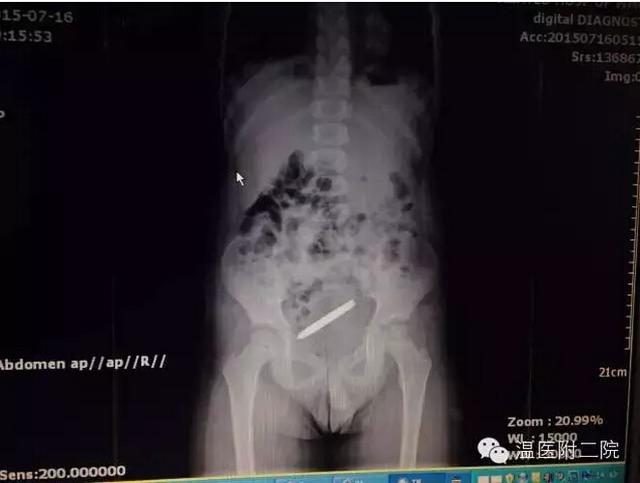

据接诊的陈聪德副主任医师说,他立即给予患儿体检、腹部立位片检查,发现螺丝刀头状金属异物在其胃内,随即邀请儿童消化科会诊,拟予行胃镜检查并取出异物。然而,在此时患儿的症状加重,出现了阵阵腹痛、呻吟不安。由于担心异物伤到消化道壁导致穿孔的可能,再次进行腹部X线拍片检查时发现,该异物竟已进入小肠内。因螺丝刀头一端尖锐,随时有可能穿破肠管。一旦肠穿孔,后果将十分严重。